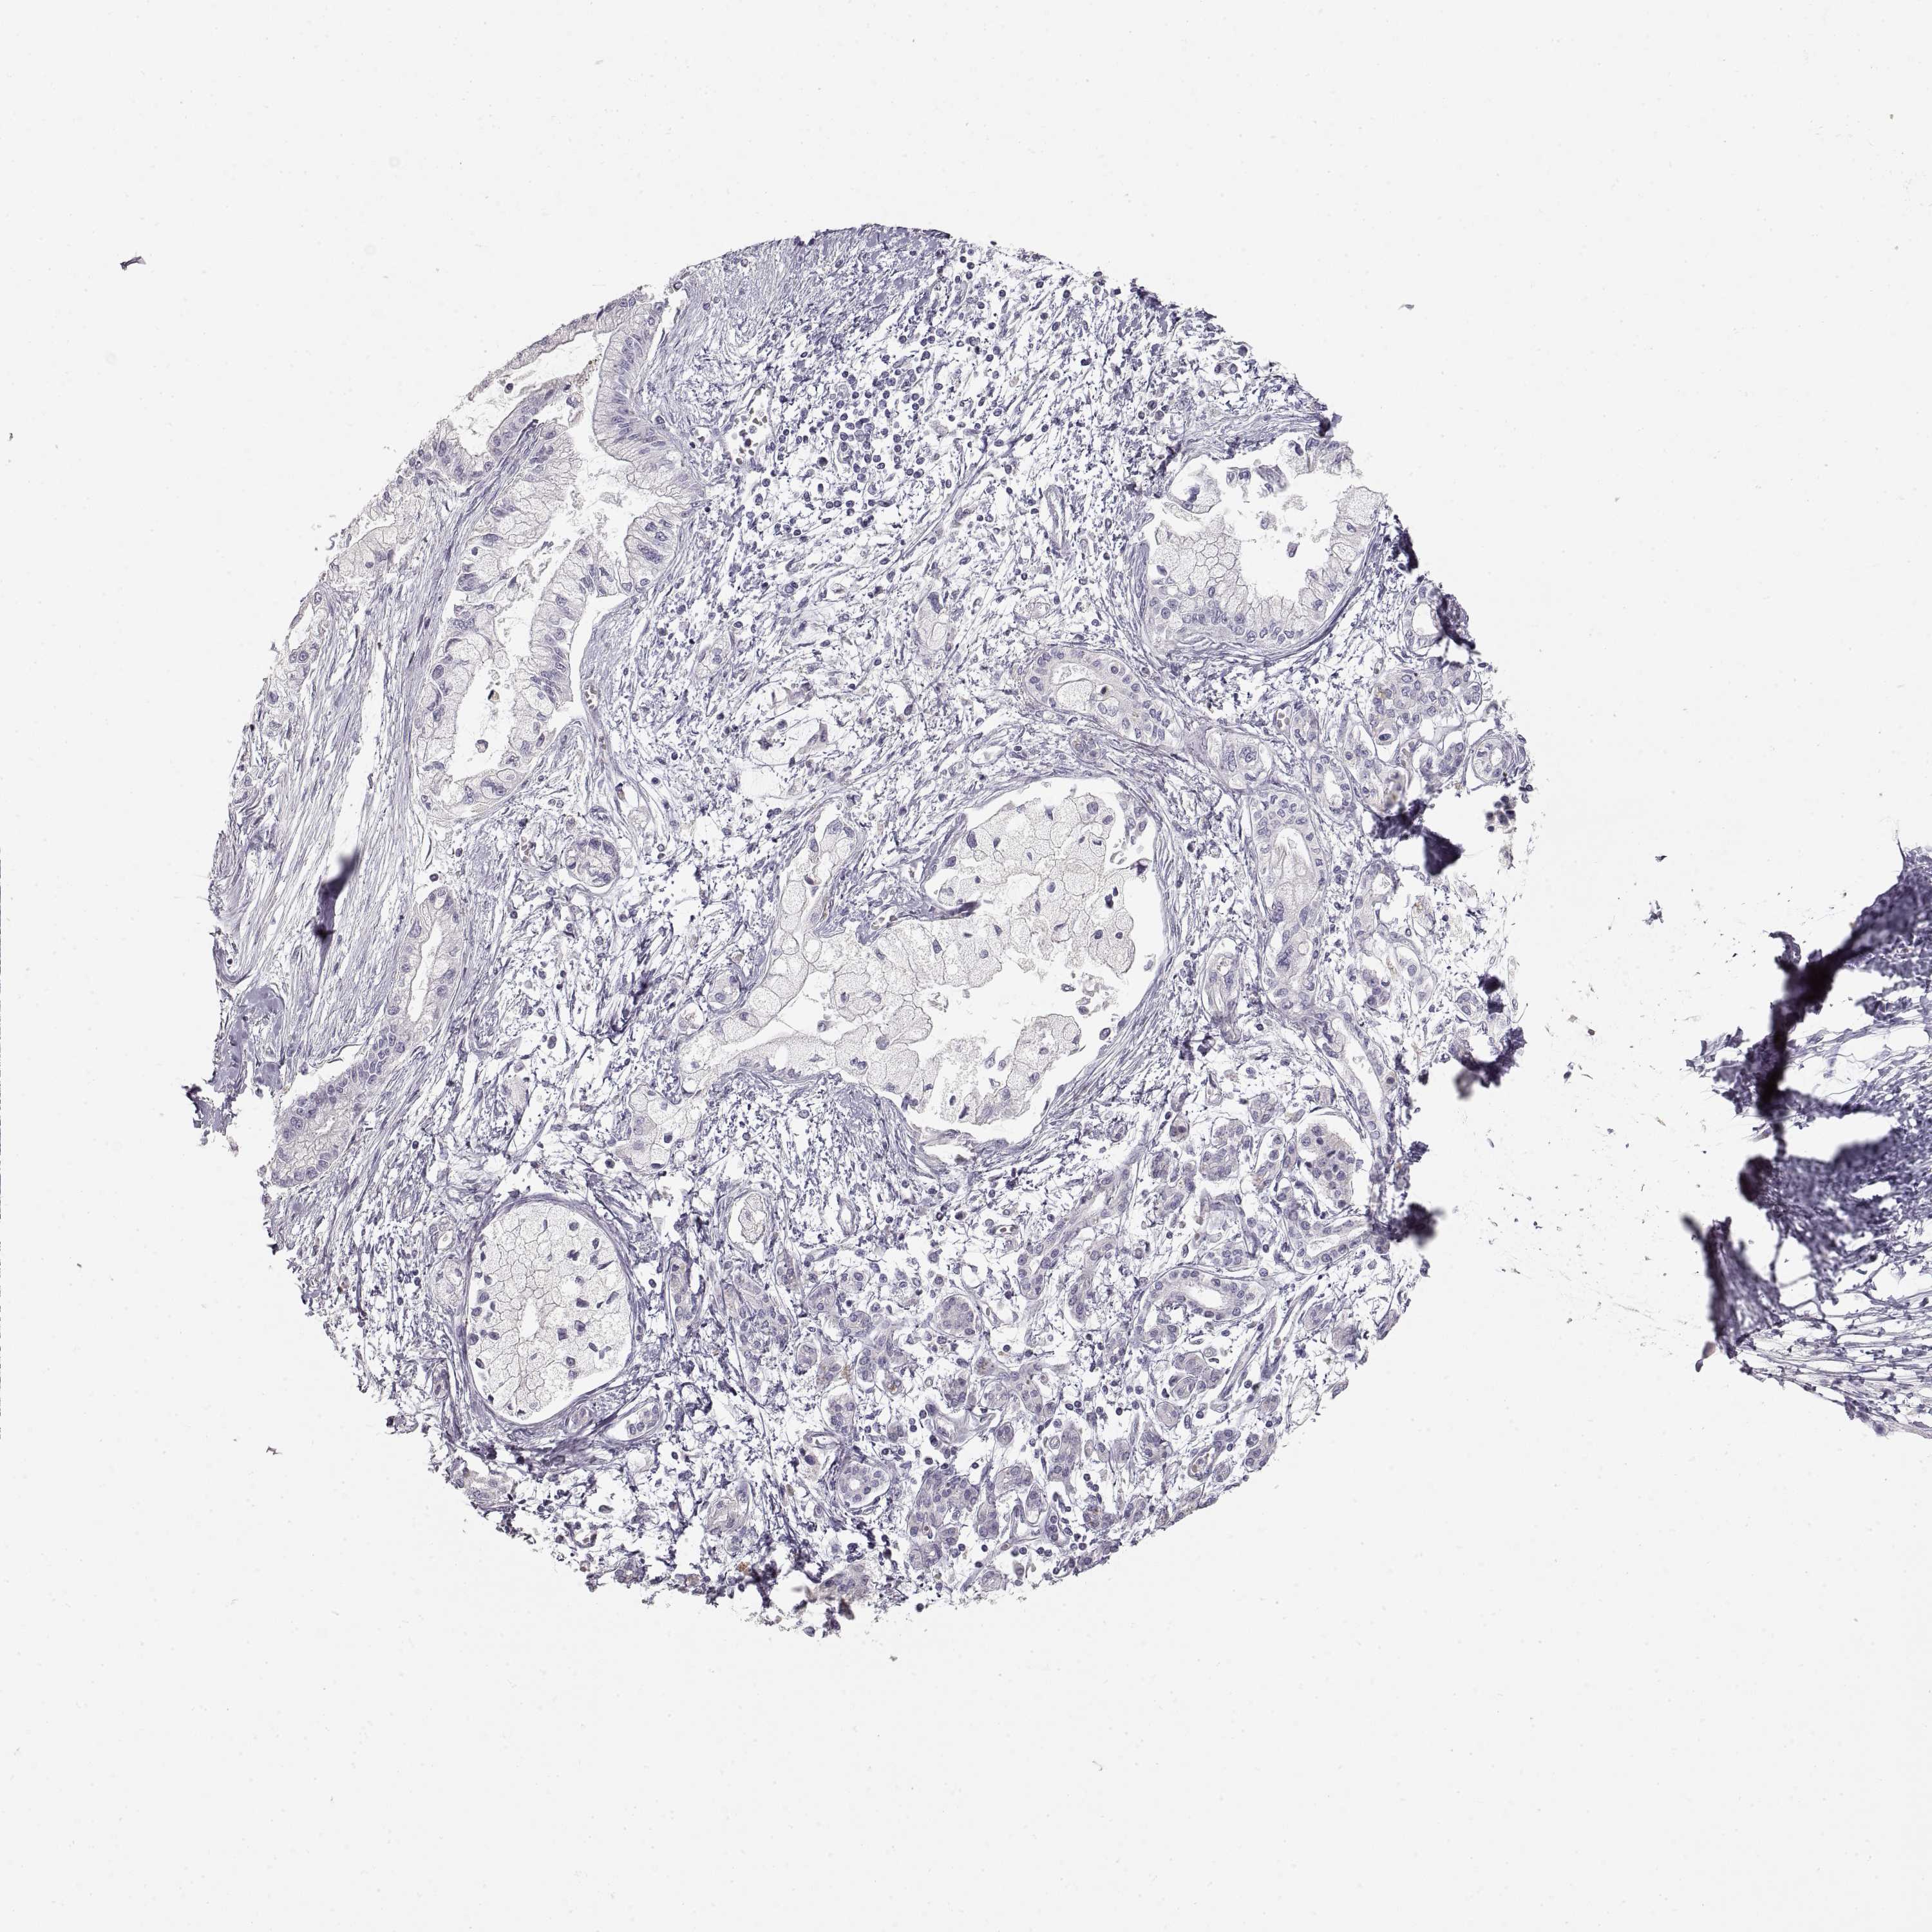

PANCREATIC CANCER - Protein expressioni

A mouse-over function shows sample information and annotation data. Click on an image to view it in a full screen mode. Samples can be filtered based on level of antibody staining by selecting one or several of the following categories: high, medium, low and not detected. The assay and annotation is described here.

Note that samples used for immunohistochemistry by the Human Protein Atlas do not correspond to samples in the TCGA dataset.

Antibody stainingi

Antibody staining in the annotated cell types in the current human tissue is reported as not detected, low, medium, or high, based on conventional immunohistochemistry profiling in selected tissues. This score is based on the combination of the staining intensity and fraction of stained cells.

Each image is clickable and will lead to virtual microscopy that enables deeper exploration of all samples and also displays staining intensity scores, fraction scores and subcellular localization as well as patient and tissue information for each sample.

Antibody HPA054061

Antibody HPA071198

Staining

High

Medium

Low

Not detected

Intensity

Strong

Moderate

Weak

Negative

Quantity

>75%

75%-25%

<25%

None

Location

Nuclear

Cytoplasmic/membranous

Cytoplasmic/membranous,nuclear

Adenocarcinoma, NOS